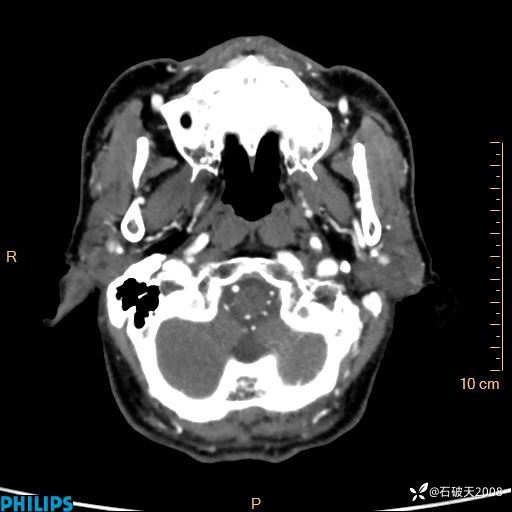

平扫